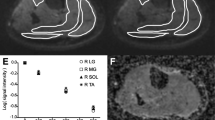

Left and right limb ROIs were defined for the rectus femoris, vastus lateralis, vastus intermedius, vastus medialis, semimembranosus, semitendinosus, biceps femoris, adductor magnus, sartorius, gracilis, tibialis anterior, peroneus longus, lateral gastrocnemius, medial gastrocnemius, soleus and tibialis posterior muscles (Fig. 1a). The ROIs were transferred to the co-registered parameter maps, minor position adjustments to account for imperfect registration were performed as necessary and the mean value for each muscle ROI was recorded. To provide summary measures, the mean of all individual-muscle ROI-means for each subject was calculated for each measure separately at thigh and at calf level. To assess inter-observer reliability, a second observer (J.M.; a neurologist with 3 years’ experience in neuromuscular imaging) independently defined ROIs using the same method on one acquisition from each of the 15 subjects with repeat examinations. Image data were inspected visually and ROI values originating from areas of gross artefact were excluded from the analysis.

Sample images from a single volunteer (a 24-year-old man, both thighs and calves). a Unprocessed Dixon acquisition (TE = 3.45 ms) used for definition of ROIs demonstrated on left thigh and calf. b B1 field map demonstrating reduced B1 anteriorly on right and posteriorly on left (arrows). All images are axial with standard orientation (anterior at top of image, subject’s right hand side at left of image). ROI labels in the thigh: RF rectus femoris, VM vastus medialis, VI vastus intermedius, VL vastus lateralis, Sa sartorius, SM semimembranosus, ST semitendinosus, BF biceps femoris (long head), AM adductor magnus, G gracilis. ROI labels in the calf: TA tibialis anterior, TP tibialis posterior, PL peroneus longus, So soleus, MG medial head of gastrocnemius, LG lateral head of gastrocnemius

The number of images excluded from the analysis was small: nine data-sets were missing or technically non-analysable: FF—thigh 1, calf 1; T1—thigh 2, calf 4; T2—none, MTR—calf 1. In the remaining data, small fractions of individual ROIs were excluded due to local artefact, mostly B1-related signal drop-out: FF—thigh 1.7 % (16/920), calf 2.4 % (13/540); T1—thigh 24 % (219/900), calf 12 % (57/492); T2—thigh 5.4 % (51/940), calf 0.2 % (1/552), MTR—thigh 15 % (142/920), calf 5.2 % (28/540). In all subjects, asymmetric B1 deviations were observed (Fig. 1b) with B1 reduced anteriorly on the right and posteriorly on the left. This was evident at the calf level but more prominent in the thigh, particularly affecting the right rectus femoris and vastus medialis. This artefact prevented measurement within right rectus femoris in 45/47 T1 maps, 41/47 MTR maps and within right vastus medialis in 35/47 T1 maps and 33/47 MTR maps.

MRI parameter maps from a representative subject are depicted in Fig. 2. Individual muscle values for each MRI measure in all 47 subjects are shown in Fig. 3. FF and T2 were similar in the left and right limbs, suggesting asymmetric B1 variations did not unduly influence these measures. Between muscles, FF differed significantly (ANOVA, p < 0.001 at both calf- and thigh-level). Group-mean sartorius FF was higher than all other thigh-level muscles (p < 0.01 for semimembranosus, p < 0.001 for all other muscles), whilst the rectus femoris FF was lower than most other thigh muscles (p < 0.01 vs gracilis, vastus lateralis; p < 0.001 vs sartorius, semimembranosus, biceps femoris and adductor magnus). Similarly, in the calf soleus the FF was highest (p < 0.05 vs peroneal, p < 0.01 vs medial gastrocnemius, p < 0.001 vs each remaining muscle), whilst tibialis anterior FF was the smallest (p < 0.01 vs medial and lateral gastrocnemius, p < 0.001 vs soleus and peroneal). However, the absolute inter-muscle differences were small; FF ranging from 0.6 % in the rectus femoris to 2.9 % in the sartorius. Inter-muscle T2 differences were also significant (ANOVA, p < 0.001 at both calf and thigh-level), with the same muscles (sartorius, semimembranosus and biceps femoris in the thigh; soleus, peroneal in the calf) showing elevated T2 as elevated FF. Whilst tibialis posterior and tibialis anterior T2 times were lowest in the calf, consistent with their low FF, gracilis T2 was lowest despite this muscle’s intermediate FF.

Sample quantitative maps from a single volunteer (a 24-year-old man, left thigh and calf). a Fat fraction map (in %). b T1 map in ms at left thigh and calf level. c T2 map (in ms). d MTR map (in p.u.). All images are axial with standard orientation (anterior at top of image, right hand side at left of image)

MTR showed apparent left-right differences in some regions with lower values for right tibialis anterior, right rectus femoris and left semimembranosus, corresponding to the areas of maximum B1 deviation. Excepting these ROIs, MTR was similar across all thigh and calf muscles (range, 31.7-33.2 p.u.). Mean T1 similarly varied between left and right limbs in these muscles suggesting incomplete B1 inhomogeneity correction, but was otherwise consistent across the remaining muscles (1,240-1,370 ms).